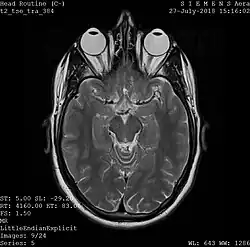

Magnetic resonance imaging

A magnetic resonance imaging instrument (MRI scanner), or "nuclear magnetic resonance (NMR) imaging" scanner as it was originally known, uses powerful magnets to polarize and excite hydrogen nuclei (i.e., single protons) of water molecules in human tissue, producing a detectable signal which is spatially encoded, resulting in images of the body.[12] The MRI machine emits a radio frequency (RF) pulse at the resonant frequency of the hydrogen atoms on water molecules. Radio frequency antennas ("RF coils") send the pulse to the area of the body to be examined. The RF pulse is absorbed by protons, causing their direction with respect to the primary magnetic field to change. When the RF pulse is turned off, the protons "relax" back to alignment with the primary magnet and emit radio-waves in the process. This radio-frequency emission from the hydrogen-atoms on water is what is detected and reconstructed into an image. The resonant frequency of a spinning magnetic dipole (of which protons are one example) is called the Larmor frequency and is determined by the strength of the main magnetic field and the chemical environment of the nuclei of interest. MRI uses three electromagnetic fields: a very strong (typically 1.5 to 3 teslas) static magnetic field to polarize the hydrogen nuclei, called the primary field; gradient fields that can be modified to vary in space and time (on the order of 1 kHz) for spatial encoding, often simply called gradients; and a spatially homogeneous radio-frequency (RF) field for manipulation of the hydrogen nuclei to produce measurable signals, collected through an RF antenna.

Like CT, MRI traditionally creates a two-dimensional image of a thin "slice" of the body and is therefore considered a tomographic imaging technique. Modern MRI instruments are capable of producing images in the form of 3D blocks, which may be considered a generalization of the single-slice, tomographic, concept. Unlike CT, MRI does not involve the use of ionizing radiation and is therefore not associated with the same health hazards. For example, because MRI has only been in use since the early 1980s, there are no known long-term effects of exposure to strong static fields (this is the subject of some debate; see 'Safety' in MRI) and therefore there is no limit to the number of scans to which an individual can be subjected, in contrast with X-ray and CT. However, there are well-identified health risks associated with tissue heating from exposure to the RF field and the presence of implanted devices in the body, such as pacemakers. These risks are strictly controlled as part of the design of the instrument and the scanning protocols used.

Because CT and MRI are sensitive to different tissue properties, the appearances of the images obtained with the two techniques differ markedly. In CT, X-rays must be blocked by some form of dense tissue to create an image, so the image quality when looking at soft tissues will be poor. In MRI, while any nucleus with a net nuclear spin can be used, the proton of the hydrogen atom remains the most widely used, especially in the clinical setting, because it is so ubiquitous and returns a large signal. This nucleus, present in water molecules, allows the excellent soft-tissue contrast achievable with MRI.[13]